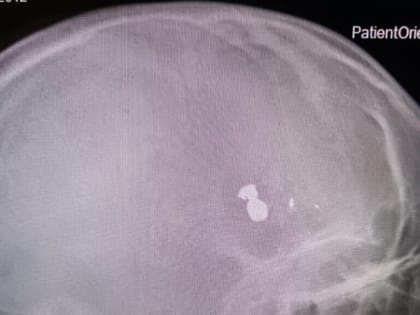

12-летний мальчик получил огнестрельное ранение в Дергачах

Медицинская помощь была оказана незамедлительно, и ребенок пришел в сознание.